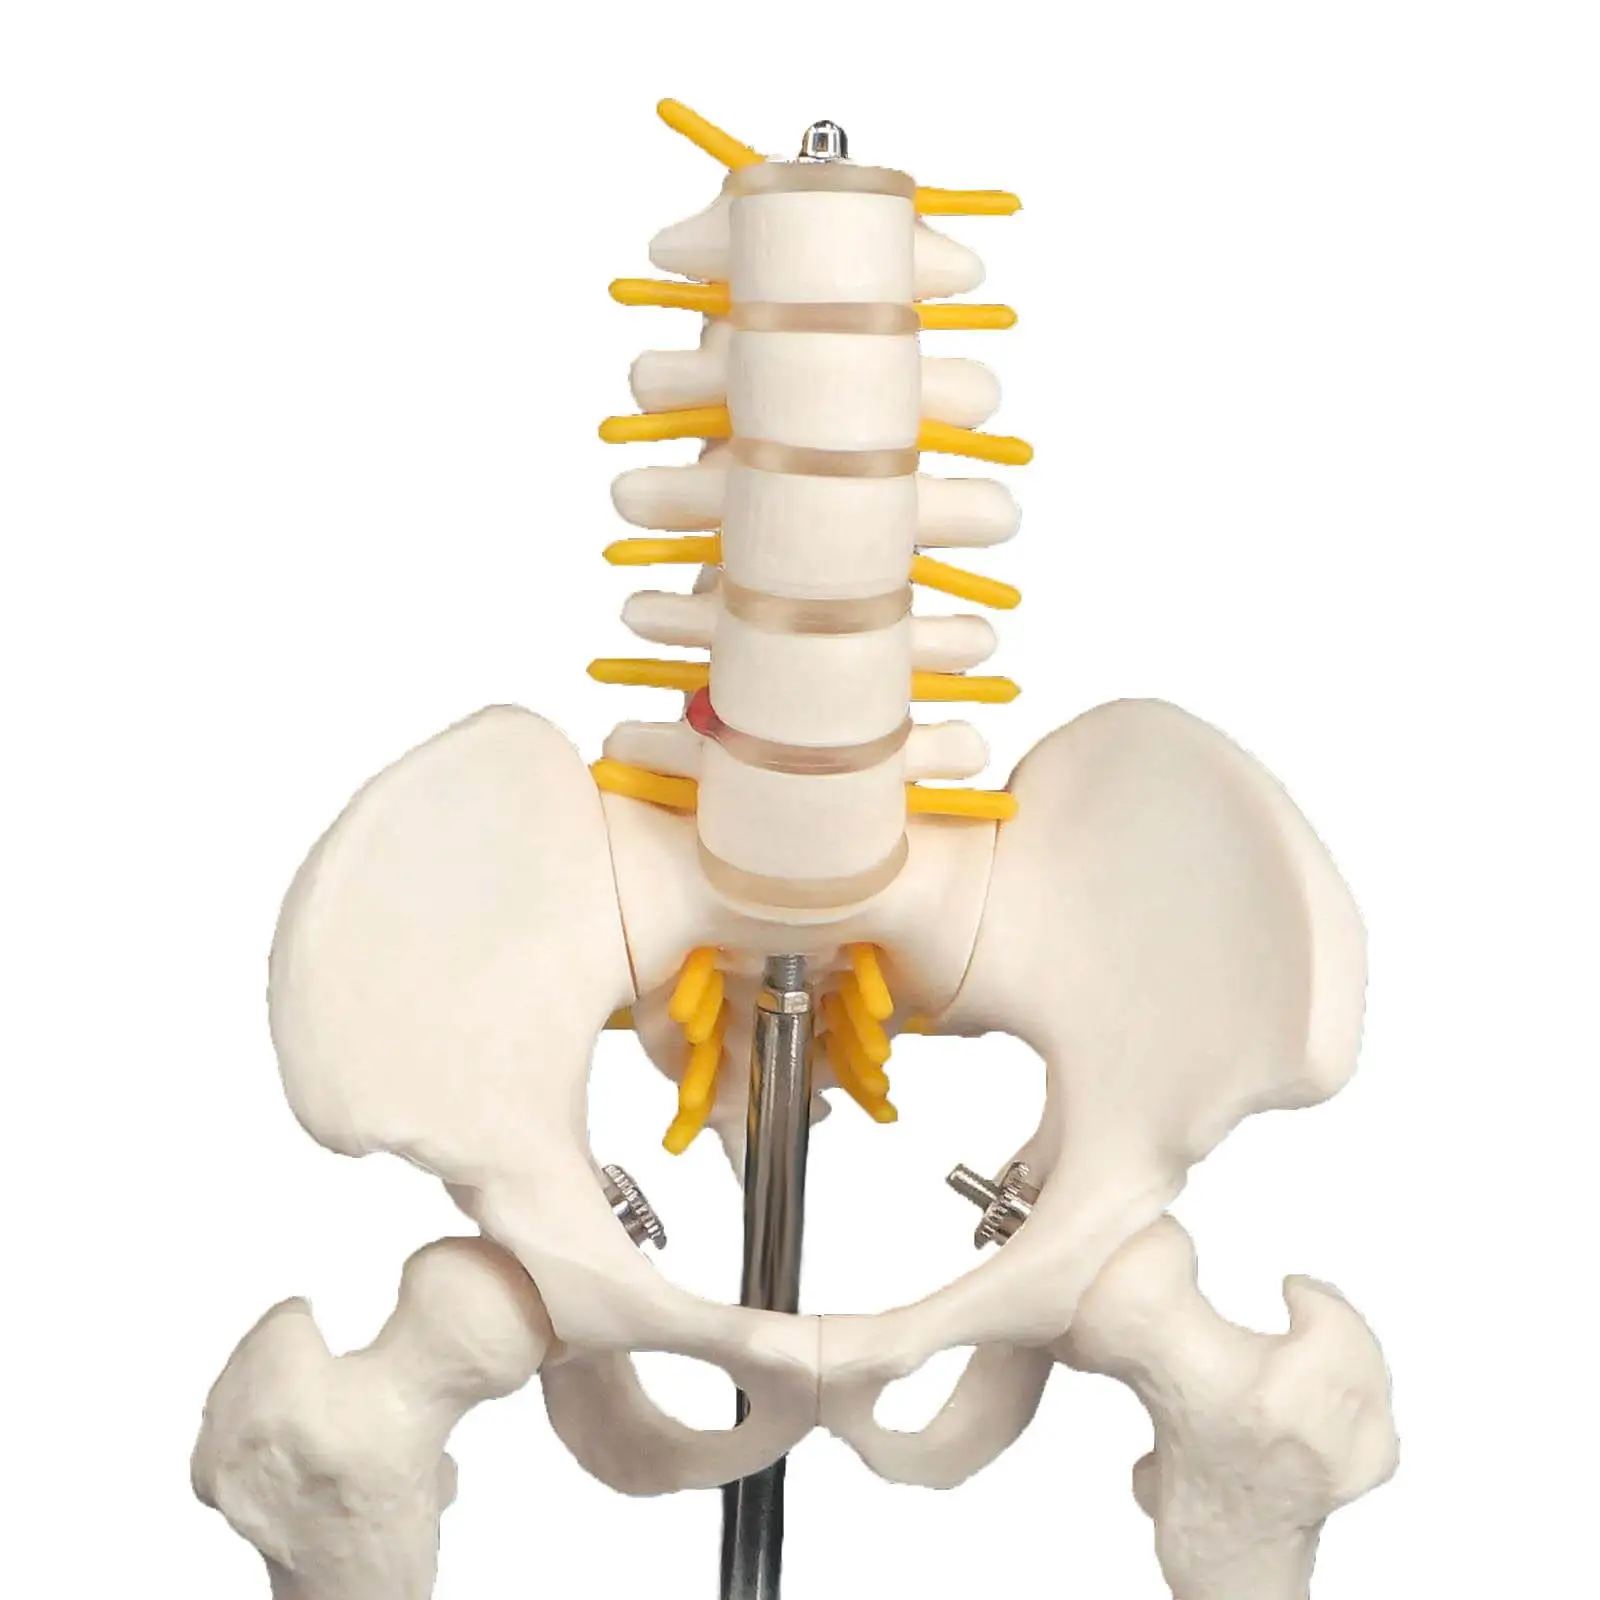

Структура позвоночника: сегменты и тазовые отделы в фотографиях